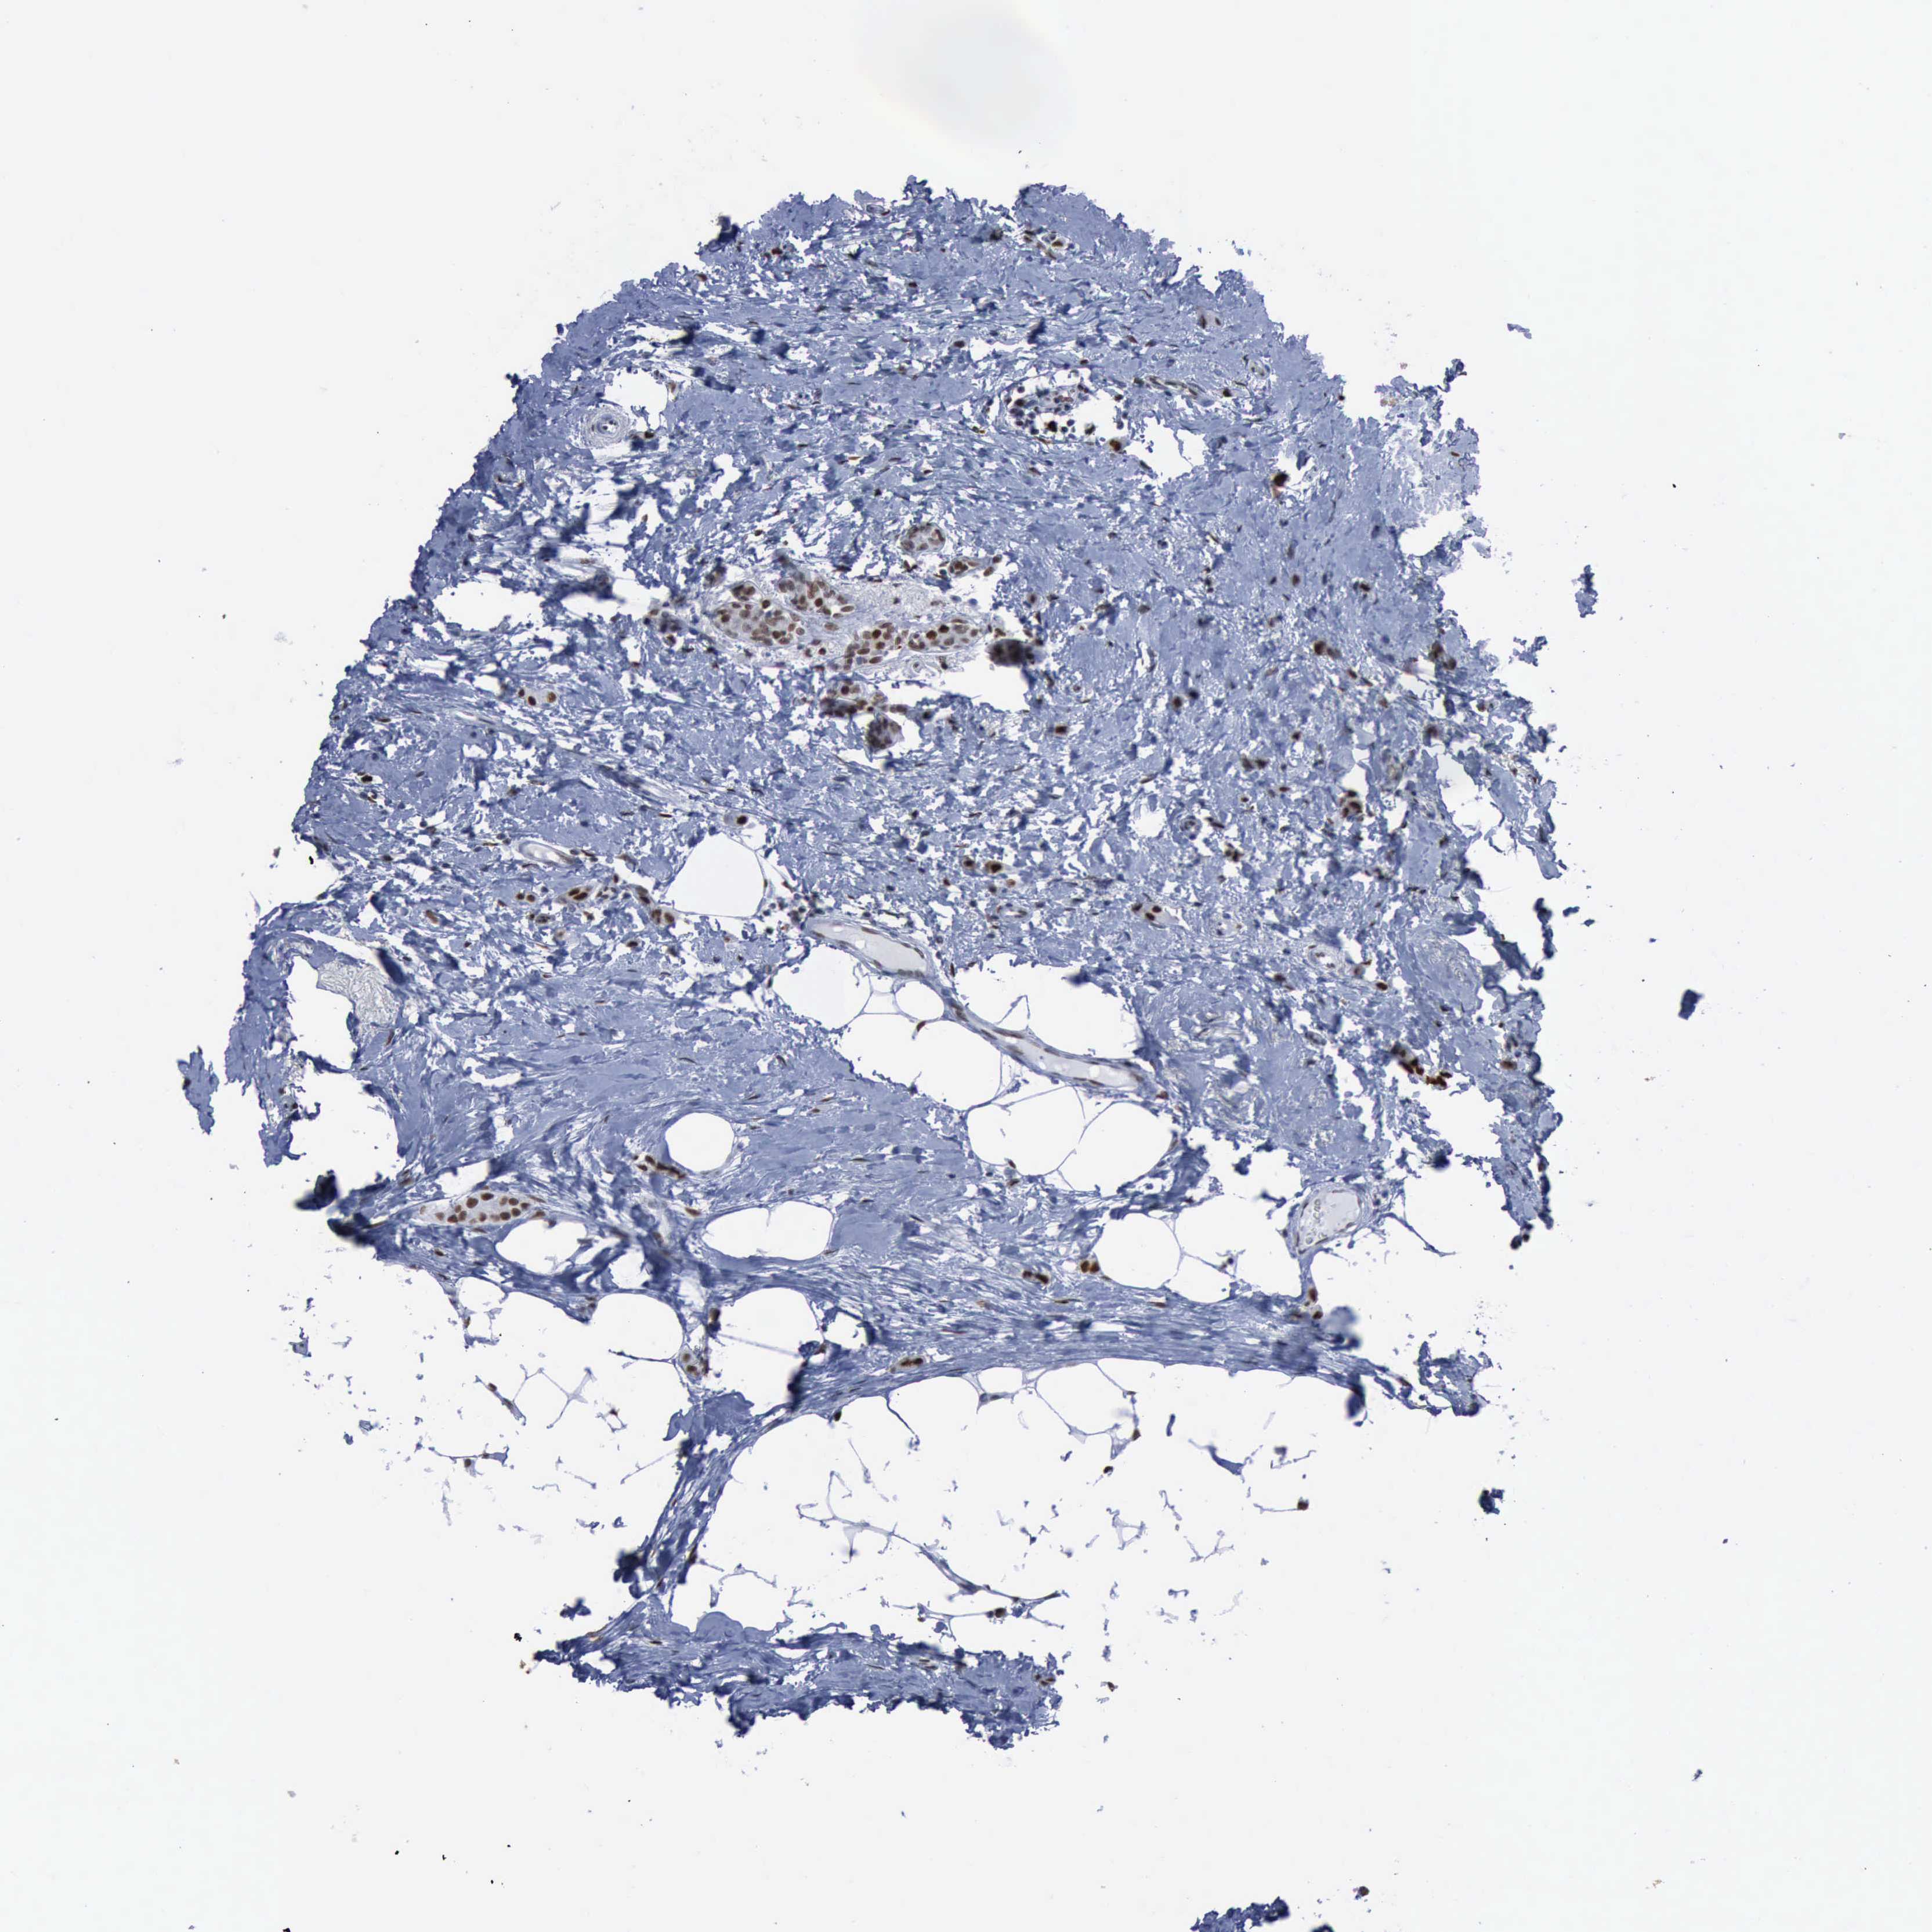

CANCER BREAST CANCER Show tissue menu

BRCA TCGA BRCA VALIDATION PROTEIN EXPRESSION

ANTIBODIES

AND

VALIDATION